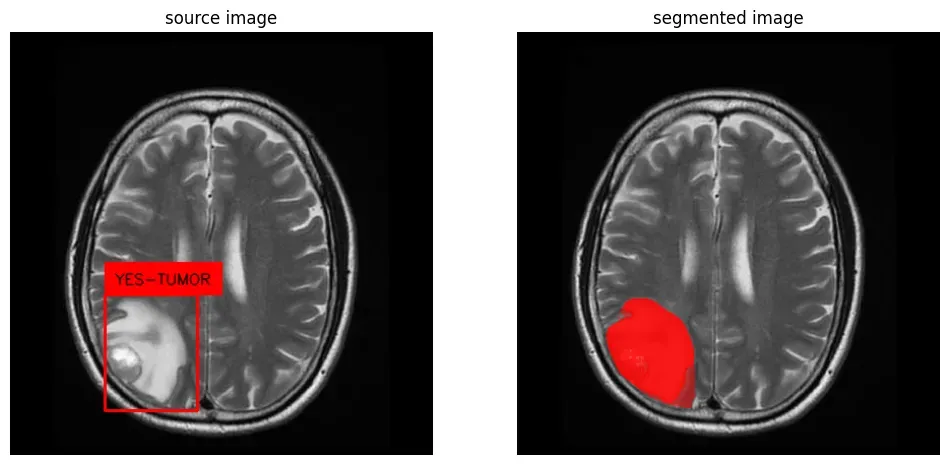

In object detection tasks, objects are represented by bounding boxes, which are like drawing a rectangle around the object. These rectangles give a general idea of the object's location, but they don't show the exact shape of the object. They may also include parts of the background or other objects inside the rectangle, making it difficult to separate objects from their surroundings.

Segmentation masks, on the other hand, are like drawing a detailed outline around the object, following its exact shape. This allows for a more precise understanding of the object's shape, size, and position.

Generate Segmentation Mask with Bounding Box

Now that you know how to generate a mask for all objects in an image, let’s see how you can use a bounding box to focus SAM on a specific portion of your image.

To extract masks related to specific areas of an image, import the SamPredictor and pass your bounding box through the mask predictor’s predict method. Note that the mask predictor has a different output format than the automated mask generator. The bounding box format for the SAM model should be in the form of [x_min, y_min, x_max, y_max] np.array.